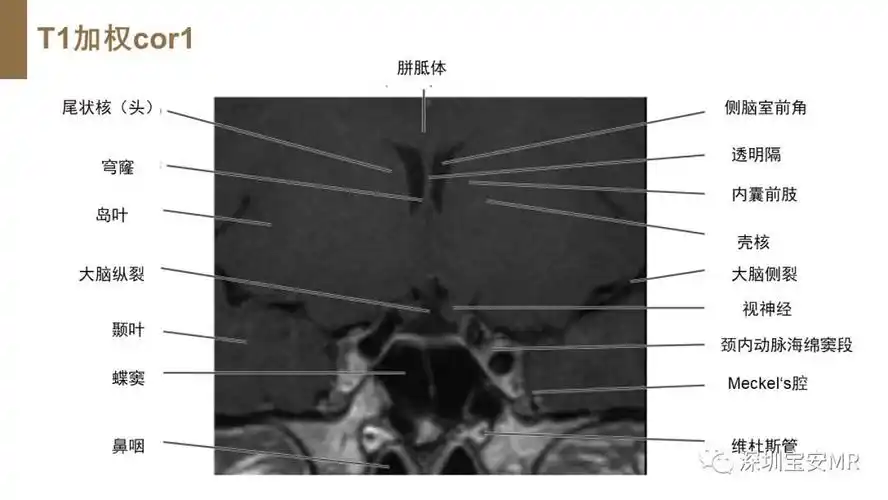

垂体磁共振影像解剖